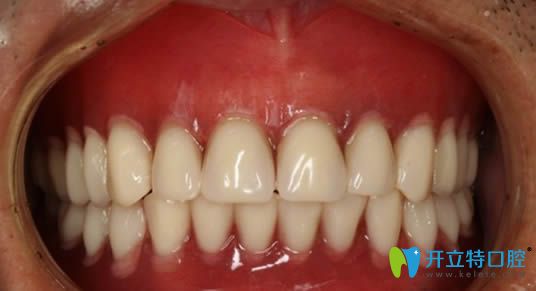

我?guī)Я?0年的活動(dòng)假牙,終于換成了種植牙:

孩子看到我為牙齒缺失的問題失落,再次帶我去到了杭州美奧口腔進(jìn)行了檢查。我還悔恨當(dāng)初沒有做種牙卻讓活動(dòng)假牙害我一生呢,但醫(yī)生讓我再次看到了希望~

杭州美奧口腔的醫(yī)生說,我這種情況屬于高難度種植,一般牙科是無(wú)法種牙的,就這樣我懷著期盼的心在杭州美奧做了全口即刻種植牙。

在杭州美奧口腔做完全口即刻種植牙后的照片

在這里提醒大家,若條件允許,請(qǐng)優(yōu)先考慮種植牙而非活動(dòng)假牙。我個(gè)人體驗(yàn)到種植牙的咀嚼功能幾乎與真牙無(wú)異,它對(duì)日常飲食的影響極大。因此,希望大家不要因?yàn)閮r(jià)格因素而將就,畢竟種植牙的高性價(jià)比是不容忽視的。